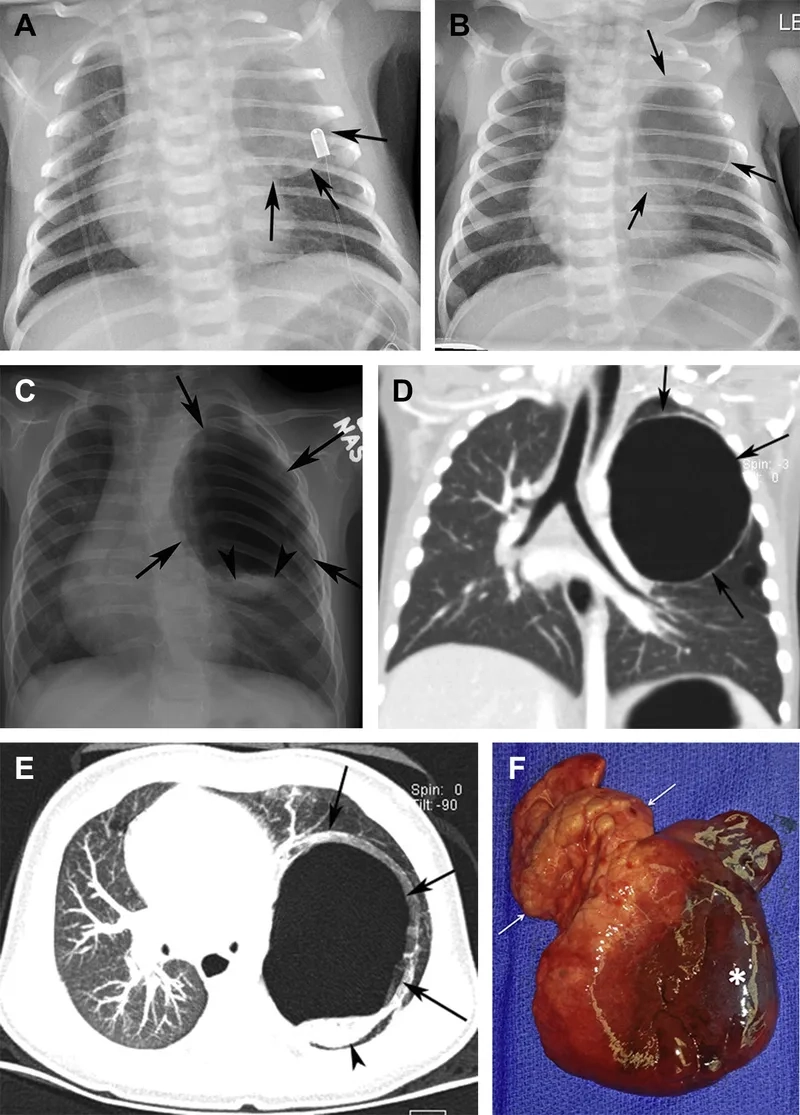

Detecting mesothelioma for timely intervention